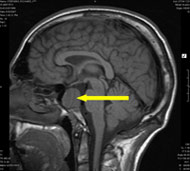

Процедуры визуализации. Магнитно-резонансная томография (МРТ) обычно применяется для постановки диагноза при опухолях головного мозга. Во время МРТ используются магнитные поля и радиоволны, которые генерируют изображение головного мозга. В некоторых случаях в вену руки вводится контрастное вещество до начала проведения МРТ. Несколько специальных изображений МРТ могут помочь врачу оценить ситуацию и назначить план лечения, включая проведение функциональной МРТ, перфузионной МРТ и магнитно-резонансной спектроскопии.